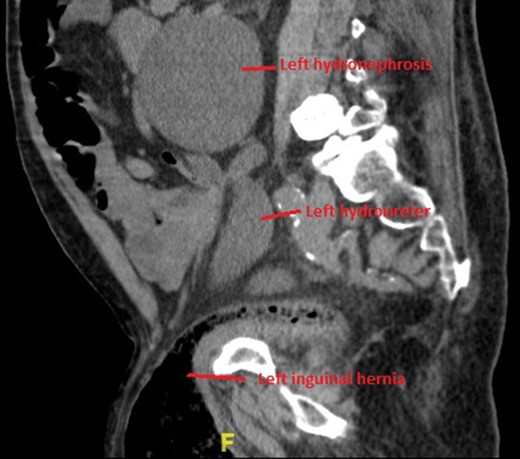

Non-contrast CT of the chest, abdomen and pelvis was performed on admission looking for malignancy considering his visible haematuria and significant unintentional weight loss. This demonstrated severe bilateral hydronephrosis and hydroureter, which was more prominent on the left side (Figs 2–4). The left ureter tapered in the pelvis and neither the bladder nor either ureter was seen in the inguinal canal and a large, left-sided inguinoscrotal hernia was seen containing distal colon. Bilateral loss of renal cortical thickness, a potassium of 6.0 mmol/L and an eGFR of 9 mL/min was suggestive of chronically obstructed kidneys.

Sagittal section of CT demonstrating large left hydronephroureter and left inguinal hernia.